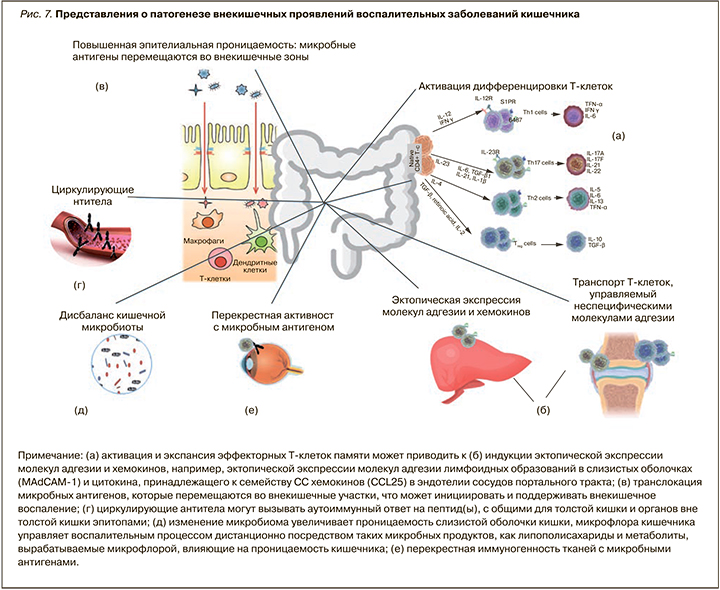

По современным представлениям, внекишечные проявления считаются результатом антиген-специфического иммунного ответа кишечника на клетки вне кишки либо независимого воспалительного события, которое инициируется в результате наличия генетических факторов риска и/или факторов риска окружающей среды. Особый вклад в патогенез многих внекишечных проявлений при ВЗК вносит нарушение микробиома кишки. Так, у пациентов со спондилоартритом наблюдается снижение микробного разнообразия и увеличение численности Ruminococcus gnavus и рода Dialister, что положительно коррелирует с активностью заболевания [17], у пациентов с псориазом снижается количество фекальных Saccharomyces cerevisiae [18]. Снижение фекального микробного разнообразия рядом авторов выявлено также при первичном склерозирующем холангите (ПСХ) [19] и воспалительных заболеваниях глаз [20]. Ciccia F. et al. (2015) и Cuthbert R.J. et al. (2017) продемонстрировали, что изменение микробиоты кишечника у пациентов с ВЗК и анкилозирующим спондилоартритом вызывает активацию иннантного иммунитета и выступает триггером для дифференцировки лимфоцитов (IL-C3s), чувствительных к интерлейкину 23 (ИЛ-23) [21, 22]. Именно лимфоциты 3-го типа (IL-C3s) обнаруживаются в значимом количестве в периферической крови, синовиальной жидкости и тканях костного мозга пациентов с анкилозирующим спондилоартритом. Большинство из активированных лимфоцитов экспрессирует хоминговый интегрин α4β7, маршрутизирующий их в ткани кишки, а молекула адгезии MAdCAM-1 широко представлена в костном мозге и эндотелии венул кишечника пациентов с анкилозирующим спондилоартритом, что играет центральную роль в привлечении IL-C3 в очаг воспаления синовиальных оболочек суставов и в рециркуляции активированных лимфоцитов между тканями кишки и сустава (рис. 7) [22].

Существует ряд потенциальных механизмов, с помощью которых микробиота кишечника управляет патогенезом внекишечных проявлений ВЗК:

1) молекулярная мимикрия (сходство микробиоты кишечника и немикробных эпитопов, находящихся вне кишечника);

2) бактериальная транслокация вследствие нарушенного кишечного барьера (микробиота или ее компоненты перемещаются из кишечника во внекишечные участки, например, в печень через портальный кровоток);

3) растворимые частицы микробного происхождения, например липополисахариды, могут попадать в кровоток и индуцировать иммунный воспалительный ответ вне кишечника.

Кроме того, дисбиотические изменения, характерные для ВЗК, включая снижение численности Faecalibacterium prausnitzii, являющихся основными продуцентами короткоцепочечных жирных кислот, приводят к нарушению кишечного барьера. Это способствует проникновению антигенов, микробов и их метаболитов в кровоток и взаимодействию их с тканями-мишенями, включая кожу, печень, слизистые оболочки вне кишечника, где они запускают или усиливают иммунные реакции, вызывающие дальнейшее повреждение тканей [23].

ВЗК ассоциированы с повышенной экспрессией провоспалительных цитокинов, в частности фактора некроза опухоли альфа (ФНО-α), ИЛ-1β, ИЛ-12, ИЛ-23 и др. Это влечет за собой модификацию силы и скорости иммунного ответа нейтрофилов («прайминг нейтрофилов») [24], инициирующих воспалительный ответ при контакте с липидными полисахаридами, которые, наряду с другими веществами, попали с системным кровотоком в отличные от кишки органы и ткани.